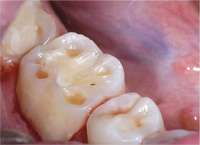

Specific training is required to treat patients with sleep-disordered breathing. Dentists should understand the nature of patients’ dysfunctions and work in a coordinated effort with sleep specialists. Dentists should discuss at length with their patients the possible side effects of oral appliance therapy, which include excessive salivation, temporomandibular joint pain, muscular pain and soreness, morning maladaptive mandibular posture, and occlusal changes (Figure 14).4

Figure 14 One of the complications of oral appliance therapy can be the development of posterior open bite. It is not common, but when it occurs usually function is not altered. It is essential that an informed risk/benefit decision is made.